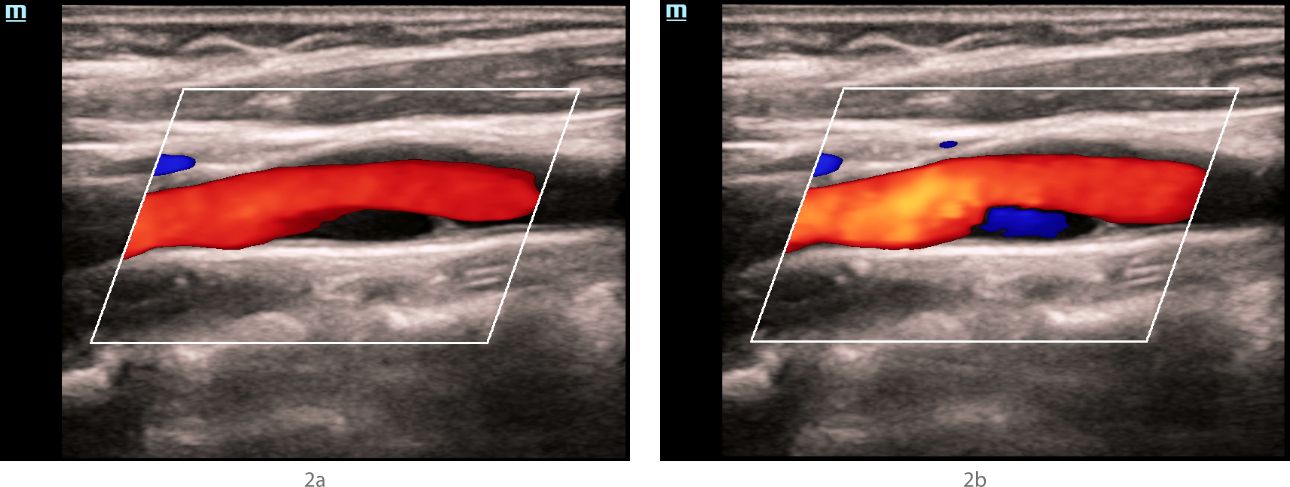

Ultrasound examination – Doppler modes

In the mode of color Doppler mapping, in the bifurcation of the left common carotid artery along the posterior wall, an anechoic zone with a smooth surface, about 1 cm long, was visualized (Fig. 2a), which was partially filled with blue blood flow (as opposed to red in the rest of the carotid arteries) (Fig. 2b). The "aliasing" effect over the zone of detected changes was not detected. In the spectral Doppler mode, in the bifurcation of the common carotid artery, the velocity parameters of blood flow were within normal limits, no areas with local changes in hemodynamics were detected (Fig. 3).

aotid-web-v-flow-fig2-pc

Fig 2. Ultrasound of the carotid sinus in the mode of color Doppler mapping.

In the bifurcation of the common carotid artery along the posterior wall, an anechoic structure is visualized, having a hyperechoic contour in the proximal shoulder, and partially filled with blue blood flow during different phases of the cardiac cycle and when the device settings are changed.